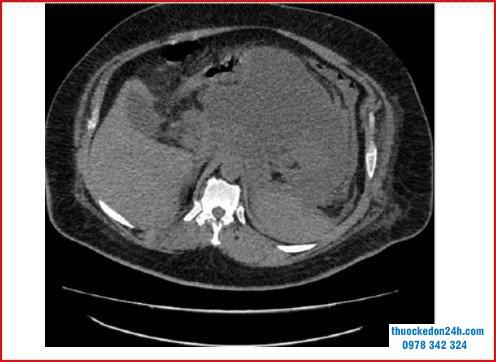

Chụp cắt lớp vi tính cho thấy nang giả tụy bị viêm